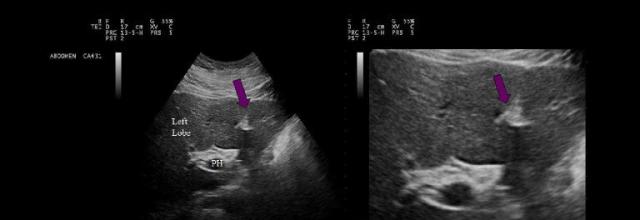

Which of the following statements is true regarding the image displayed?

The gallbladder has a normal variant called a Phrygian cap near the fundal area

the purple arrow on the images represents, which of the following structures?

Ligamentum venosum

The purple arrows point to which of the following liver structures?

Ligamentum teres